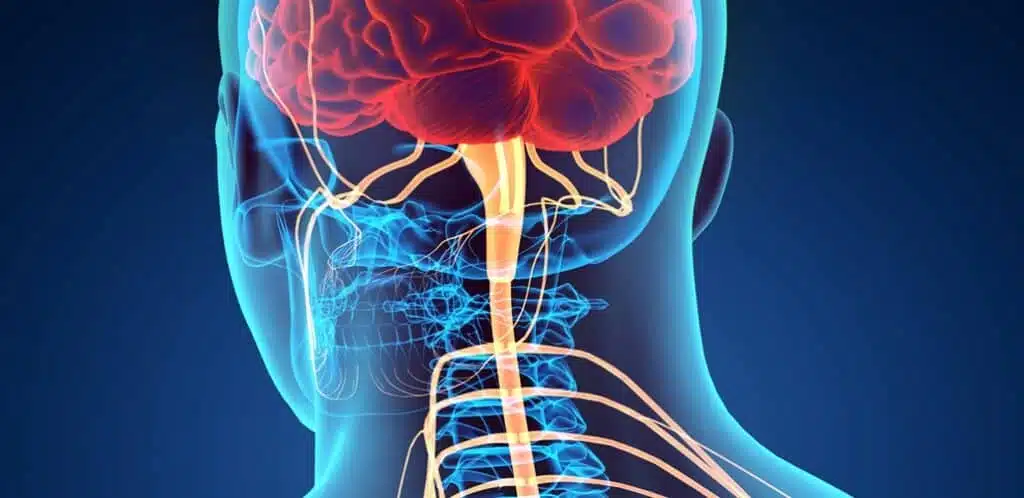

Central Pain Syndrome & Acupuncture Treatment in Tokyo

Central pain syndrome is a complex and often debilitating neurological condition that affects thousands of people worldwide. Unlike typical pain caused by injury or inflammation, central pain arises from damage or dysfunction in the central nervous system (CNS), which includes the brain and spinal cord. This article explores the causes, symptoms, diagnosis, and treatment options […]